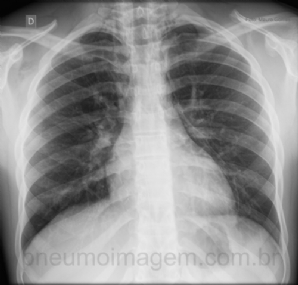

CASO CLÍNICO #2

Jovem do sexo masculino, 16 anos de idade, asmático leve sem tratamento regular, apresenta-se com intensa dispneia e dor torácica que se iniciou enquanto disputava uma partida de futebol. Qual o diagnóstico? Observe a imagem e deixe os seus comentários abaixo....